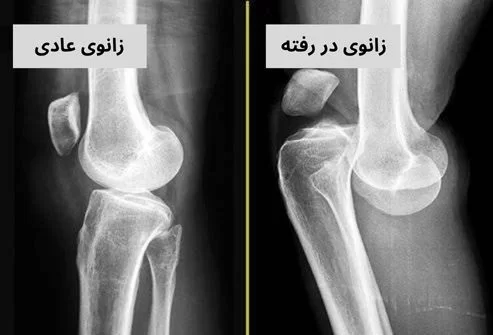

دررفتگی کشکک زانو آسیب دردناکی است که در آن استخوان کاسه زانو (کشکک) از جایگاه طبیعی خود در شیار انتهای استخوان ران خارج می شود. این آسیب معمولا به دنبال یک چرخش ناگهانی زانو یا وارد آمدن ضربه مستقیم رخ میدهد و باعث درد شدید، تورم فوری و تغییر شکل آشکار زانو میگردد. برای تشخیص دقیق و درمان موثر این آسیب، مراجعه به یک دکتر ارتوپد در مشهد یا شهرهای دیگر که متخصص مشکلات زانو باشد، ضروری است.

• مکانیسم آسیب: دررفتگی زمانی اتفاق می افتد که این استخوان به طور کامل از شیار خود خارج شود. در بیشتر موارد، کشکک به سمت بیرون زانو جابجا میشود. گاهی اوقات نیز کشکک پس از دررفتگی، به طور خودبه خود به جایگاه اصلی باز میگردد که به آن “دررفتگی گذرا” میگویند.

• تغییر شکل آشکار: زانو ظاهری عجیب پیدا میکند و برآمدگی در سمت بیرونی زانو دیده میشود، زیرا کشکک از جای خود خارج شده است.

• رادیوگرافی (اشعه ایکس): برای تایید دررفتگی، بررسی موقعیت کشکک و رد کردن شکستگی های همراه استفاده میشود.